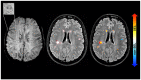

Background: Magnetic resonance imaging (MRI) markers for chronic active lesions in MS include slowly expanding lesions (SELs) and paramagnetic rim lesions (PRLs).

Methods: 61 people with MS (pwMS) followed retrospectively with MRI including baseline susceptibility-weighted imaging, and longitudinal T1 and T2-weighted scans. SELs were computed using deformation field maps; PRLs were visually identified. Mixed-effects models assessed differences in Expanded Disability Status Scale (EDSS) score changes between the group defined by the presence of SELs and or PRLs.

Results: The median follow-up time was 3.2 years. At baseline, out of 1492 lesions, 616 were classified as SELs, and 80 as PRLs. 92% of patients had ⩾ 1 SEL, 56% had ⩾ 1 PRL, while both were found in 51%. SELs compared to non-SELs were more likely to also be PRLs (7% vs. 4%, p = 0.027). PRL counts positively correlated with SEL counts (ρ= 0.28, p = 0.03). SEL + PRL + patients had greater increases in EDSS over time (beta = 0.15/year, 95% confidence interval (0.04, 0.27), p = 0.009) than SEL+PRL-patients.